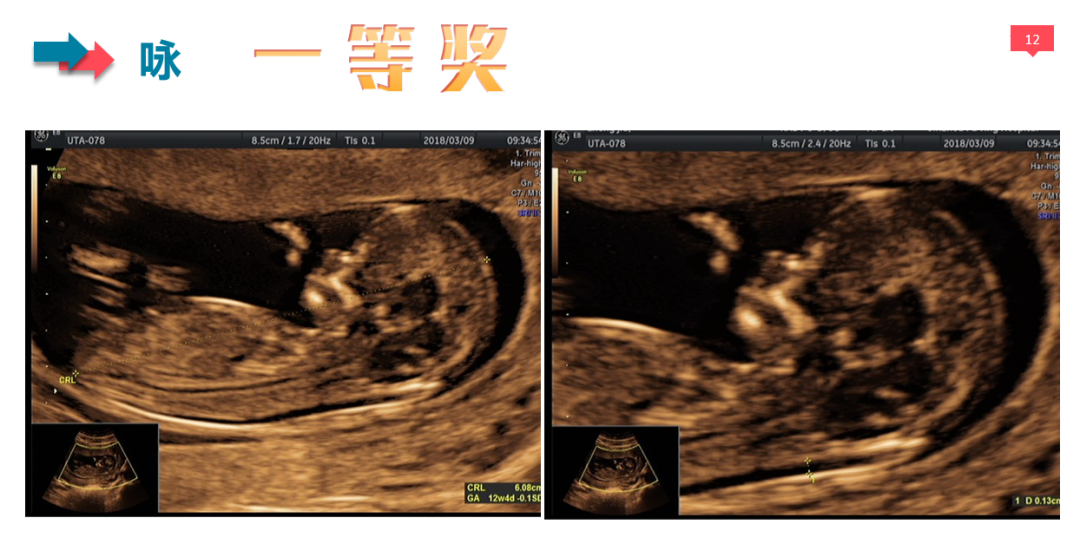

经过5位评委的独立评审和2位主任的审核,每组评选出6个作品进入更为严格的第二轮评选,第二轮评选由全体评委及审核共同对入围作品的得分点及扣分点进行逐一商确,最终每个组别分别评选出一等奖1名,二等奖2名,三等奖3名。